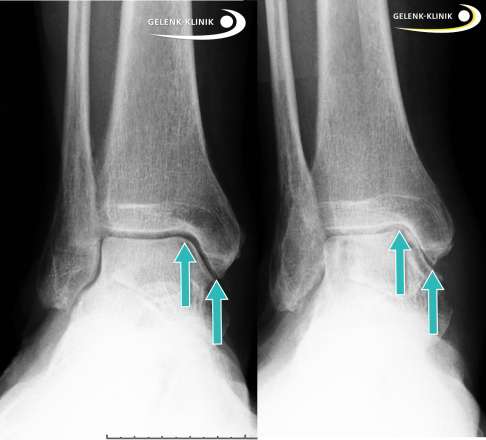

Röntgenbild des Sprunggelenks (Seitenvergleich): Links sieht man ein gesundes Sprunggelenk mit einem normal großen Gelenkspalt. Rechts ist durch die Fehlstellung eines Knick-Senkfußes oder Knickplattfußes eine Arthrose am Innenknöchel entstanden. Ursache ist die Fehlstellung des Sprungbeins in der Gabel und eine resultierende instabile Situation des Sprungbeins. Das Abstützen des Fußlängsgewölbes kann die Beschwerden verbessern. © Dr. Thomas Schneider